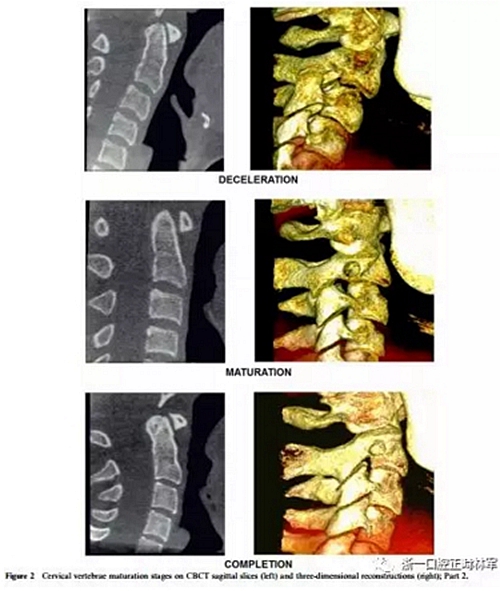

4、減速期(頸椎成熟指數(shù)-4)

預(yù)計(jì)增長(zhǎng)10-25%。椎骨C2,C3和C4的下部邊界呈現(xiàn)明顯的凹陷,并且椎骨C3和C4的體部呈現(xiàn)近似正方形的形狀。

5、成熟期(頸椎成熟指數(shù)-5)

這對(duì)應(yīng)于椎骨成熟的最后階段,預(yù)計(jì)5-10%的增長(zhǎng)。在椎骨C2,C3和C4上觀察到更明顯的凹陷。后者有方形的體部。

6、定型(頸椎成熟指數(shù)-6)

現(xiàn)階段增長(zhǎng)已經(jīng)完成。椎骨C3和C4的體部具有比水平尺寸和下邊界更大的垂直,下邊界保持明確的凹陷。